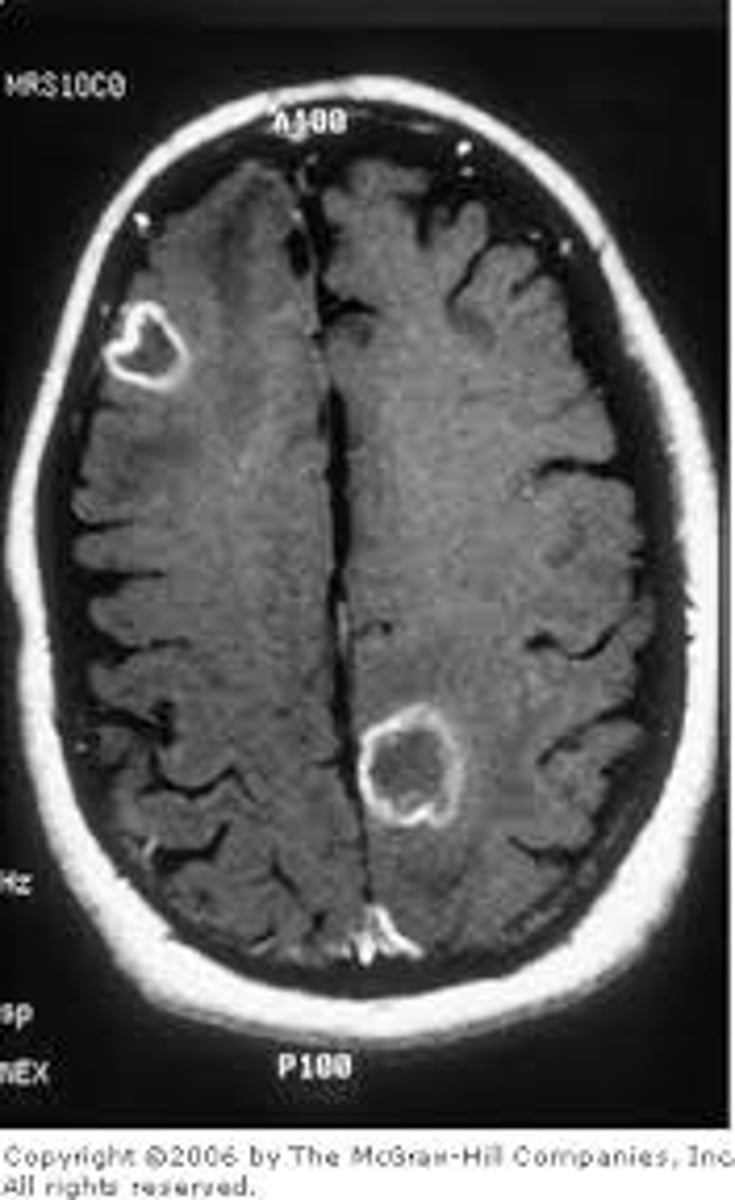

Lesioning

damage to a part of the brain that results in destruction to the neurons; can be natural (like brain injury or disease) or deliberate (surgery)